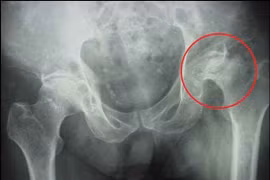

(khoahocdoisong.vn) - Lạm dụng rượu, bia, thuốc lá là nguyên nhân chủ yêu gây ra hoại tử chỏm xương đùi do làm tổn thương gây viêm mạch mạn tính và làm tắc các mao mạch nuôi dưỡng chỏm xương đùi dẫn tới hoại tử chỏm.